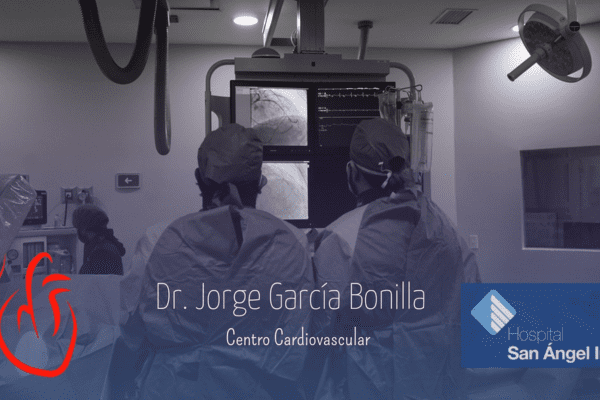

Conoce mis instalaciones y algunos casos de pacientes en mi